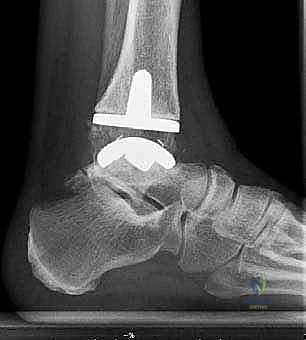

يتكون مفصل الكاحل الصناعي الحديث عادة من ثلاثة أجزاء:

* قطعة معدنية علوية: تُثبت في عظمة الظنبوب (الساق).

* قطعة معدنية سفلية: تُثبت في عظمة الكاحل.

* قطعة بلاستيكية (بولي إيثيلين عالي الكثافة): توضع بين القطعتين المعدنيتين لتنزلق بسلاسة وتمتص الصدمات، محاكيةً وظيفة الغضروف الطبيعي.

يتم تثبيت هذه الأجزاء بإحكام (إما عن طريق الضغط المباشر لتشجيع نمو العظم حولها، أو باستخدام أسمنت طبي خاص).